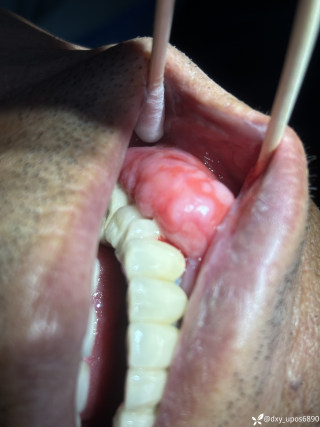

烧伤整形邹普功烧伤科医师

活动背景和目的:我从去年九月份陆续在丁香园写了几十帖有关腋臭微创手术的帖子,受到很多同行老师的关注及跟帖,其中有很多同行老师也在尝试用我的这种方法治疗狐臭,并且收到很好的效果。随着站内外科同行对狐臭微创手术的关注度日渐增高,近期受丁香园邀请,特举办一次关于狐臭微创手术的跟学练活动。这也是本人根据临床工作中的一些手术案例总结的经验,分享给大家一起交流学习。让我们一起做好除臭这件事!各位站友可点击下面狐臭专场链接交流学习(包含本人视频操作教学详解、常见问题讨论和各位站友同行的手术佳作):https://3g.dxy.cn/newh5/view/nodeActivityTopic/270第一期我给大